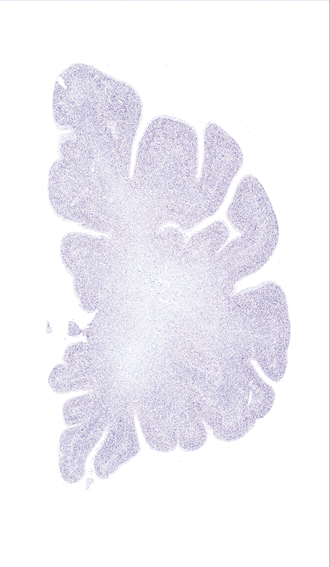

Hi-Resolution Sections · Cells (Nissl Staining) · Virtual Microscopy

Frontal sections (Nissl) from the Atlas Brain:

Slice ID:

r2-0854

Plate NR:

07-08

Position:

-26,2 mm